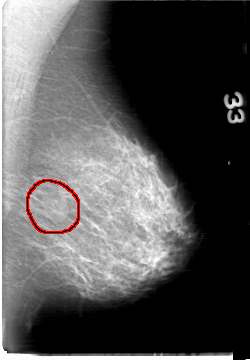

D_4058_1.LEFT_MLO

LEFT_MLO LINES 5386 PIXELS_PER_LINE 3736 BITS_PER_PIXEL 12 RESOLUTION 43.5 OVERLAY

FILE: D_4058_1.LEFT_MLO.OVERLAY

TOTAL_ABNORMALITIES 1

ABNORMALITY 1

LESION_TYPE MASS SHAPE OVAL MARGINS OBSCURED

ASSESSMENT 0

SUBTLETY 3

PATHOLOGY BENIGN

TOTAL_OUTLINES 1

BOUNDARY